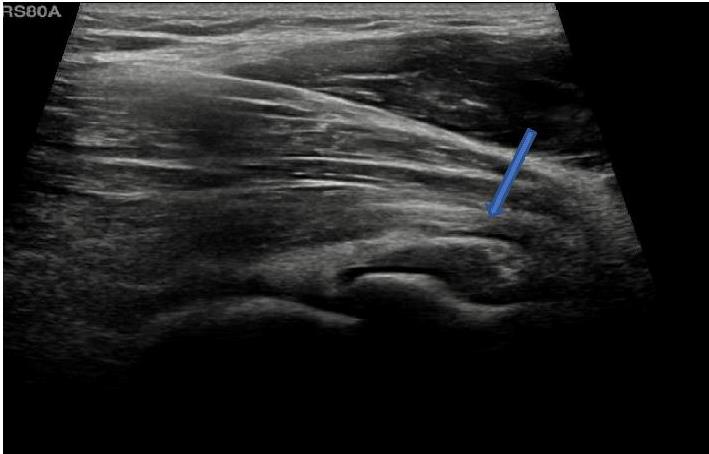

![]() |

Image A : Longtitudinal image : small effusion seen anterior to the radial head (arrow). |